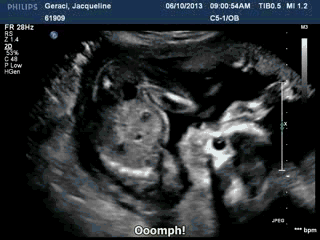

I’m not exactly sure how she got Internet access in there, but apparently baby Geraci has already started an animated GIF Tumblr.